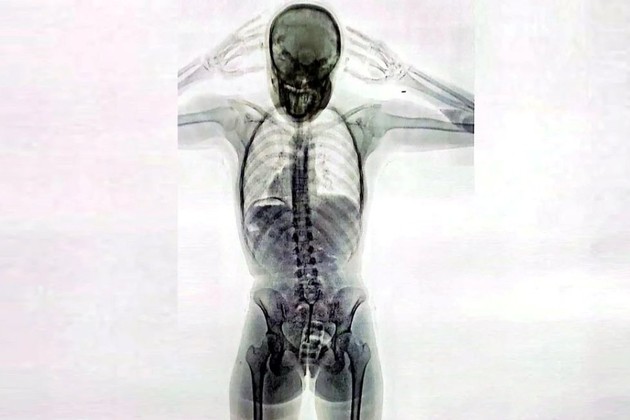

Impresionante imagen de un escáner de rayos X: una mula tenía 78 cápsulas de cocaína en el cuerpo

Ante consultas por parte de inspectores de la Aduana, la pasajera “respondió de manera incongruente y dubitativa”, lo cual levantó aún más las sospechas. Ante esta situación, agentes de la Policía de Seguridad Aeroportuaria (PSA), conjuntamente con funcionarios de la Dirección General de Aduanas y personal de AIRCOP, procedieron a realizarle un control corporal no invasivo mediante equipo de rayos X (Body Scan) y delante de la presencia de testigos.

La inspección dio pie a la revelación del delito: en las imágenes los efectivos observaron la posible presencia de elementos extraños en el organismo, concentrados en su zona genital.

En consecuencia, con la orden judicial en mano, la pasajera empezó a ser requisada hasta que en un momento confesó espontáneamente y manifestó que transportaba un paquete introducido vía vaginal. Concretamente, había introducido en su cuerpo un profiláctico con 11 cápsulas de cocaína, de aproximadamente 10 gramos cada una.

Como parte del procedimiento, la joven fue trasladada al Hospital de Ezeiza. Allí, bajo custodia de la PSA, estuvo incomunicada mientras evacuaba las cápsulas detectadas en las imágenes del escáner, las cuales finalmente fueron muchas más que 11: tenía otras 67 cápsulas en el sistema digestivo. En total, en su cuerpo llevaba 742 gramos de esa droga.